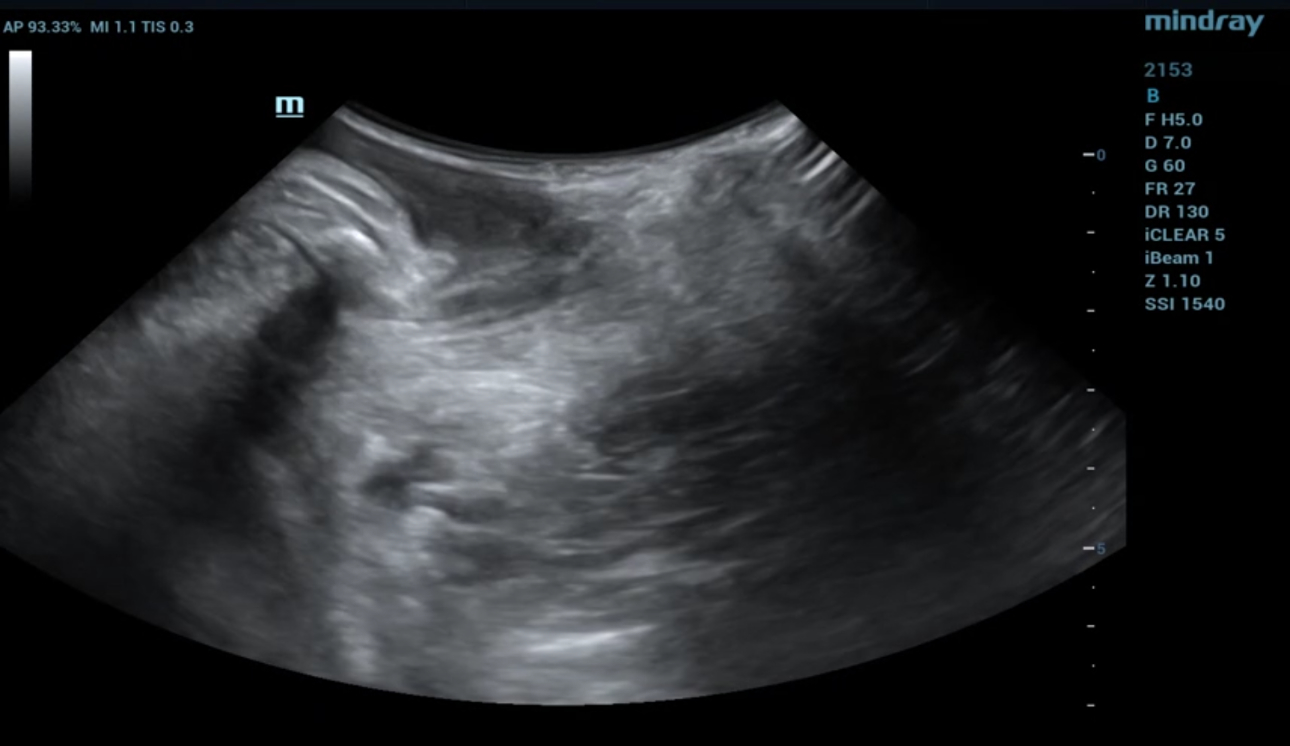

levator-trauma-fig10-pc

형상 5. 산후 9개월 이후 ipage+ 이미지